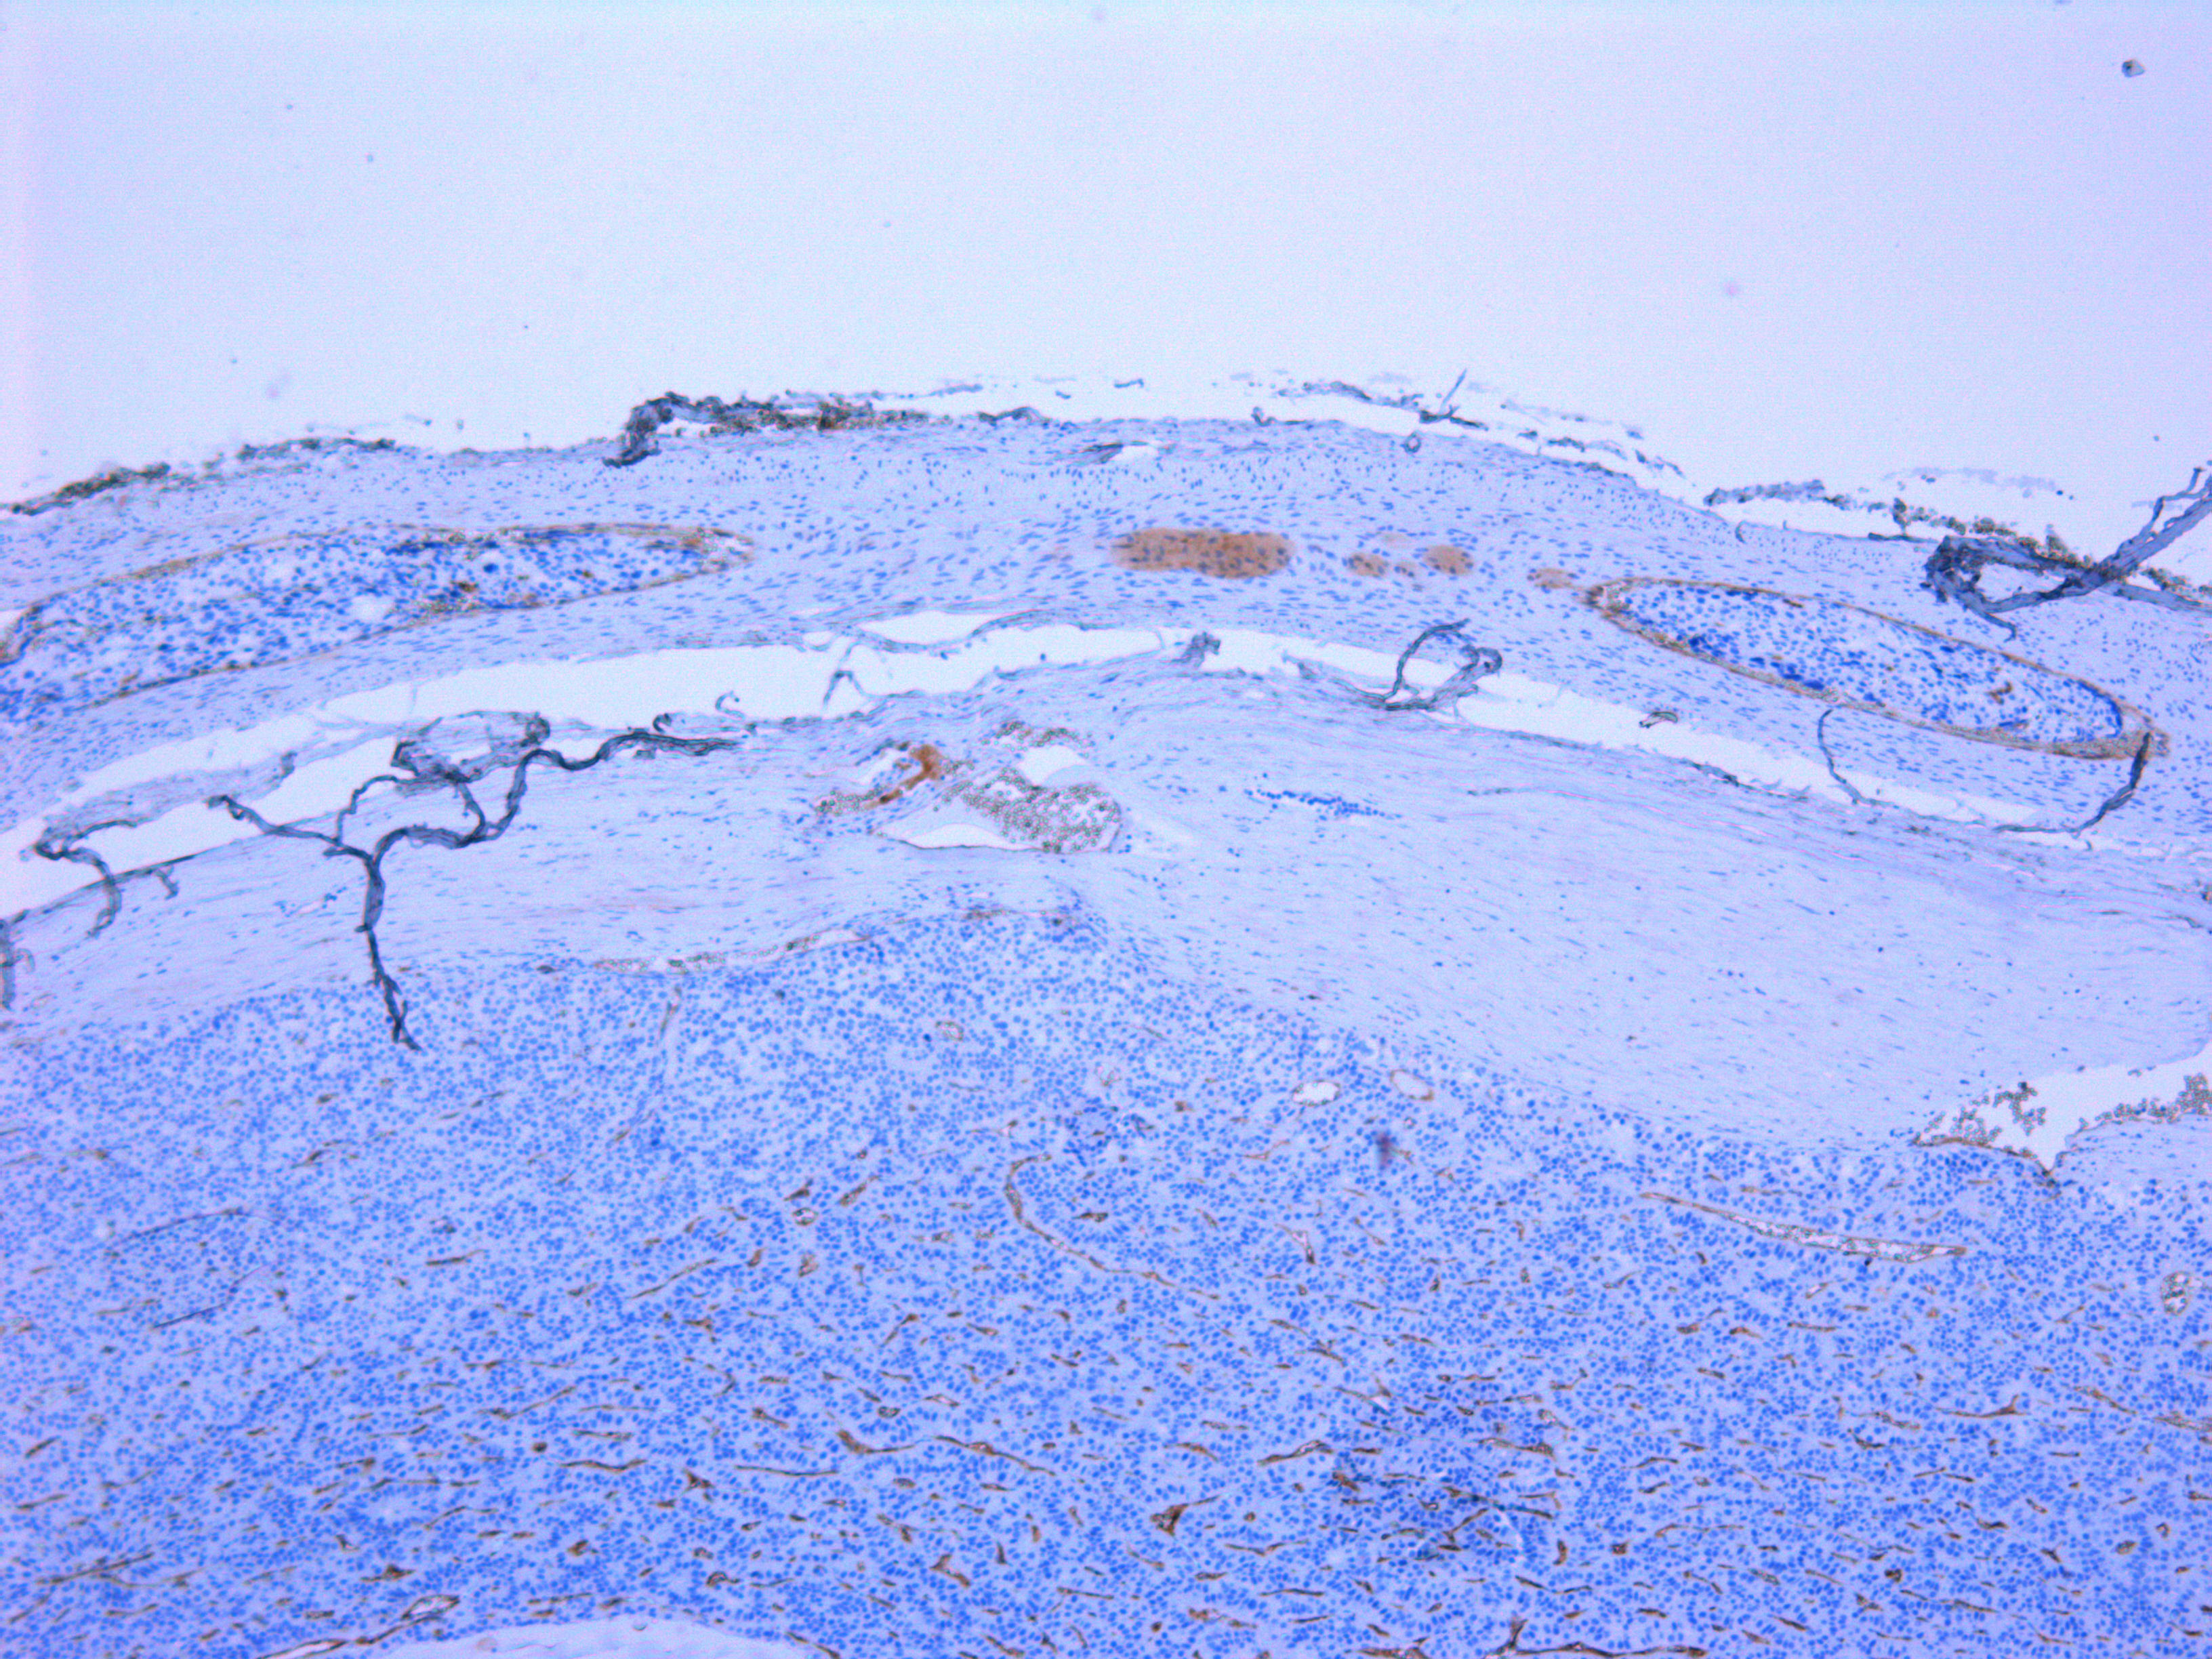

1. Рисунок 1А | |

2. Рисунок 1Б | |

3. Рисунок 2 | |